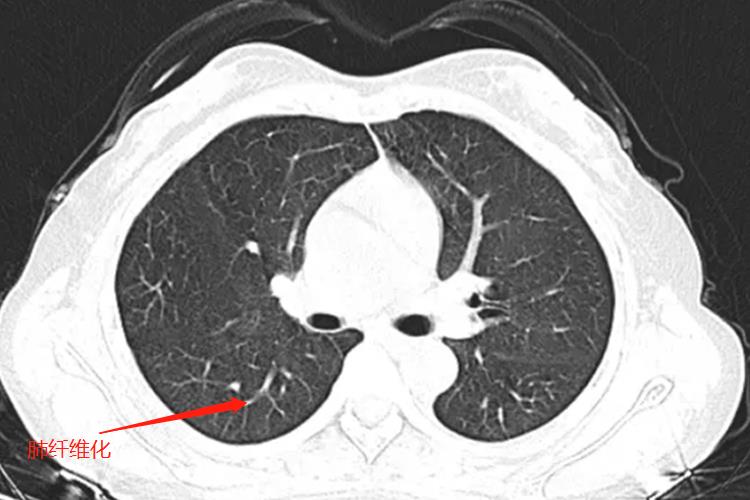

肺纤维化在CT影像学的表现主要是蜂窝肺、网格状阴影以及牵拉性支气管扩张,有时会伴随有其他形式的病变,如与磨玻璃影等。

CT在诊断肺纤维化中具有重要的价值,特征性表现为胸膜下和肺基底部的网格状阴影和蜂窝影,常伴有牵张性支气管扩张,尤其是蜂窝影;高分辨率CT上的蜂窝影指成簇的囊泡样气腔,蜂窝壁边界清楚。囊泡直径在3-10mm,偶尔可大至25mm。磨玻璃影常见,但病变范围少于网格状影。